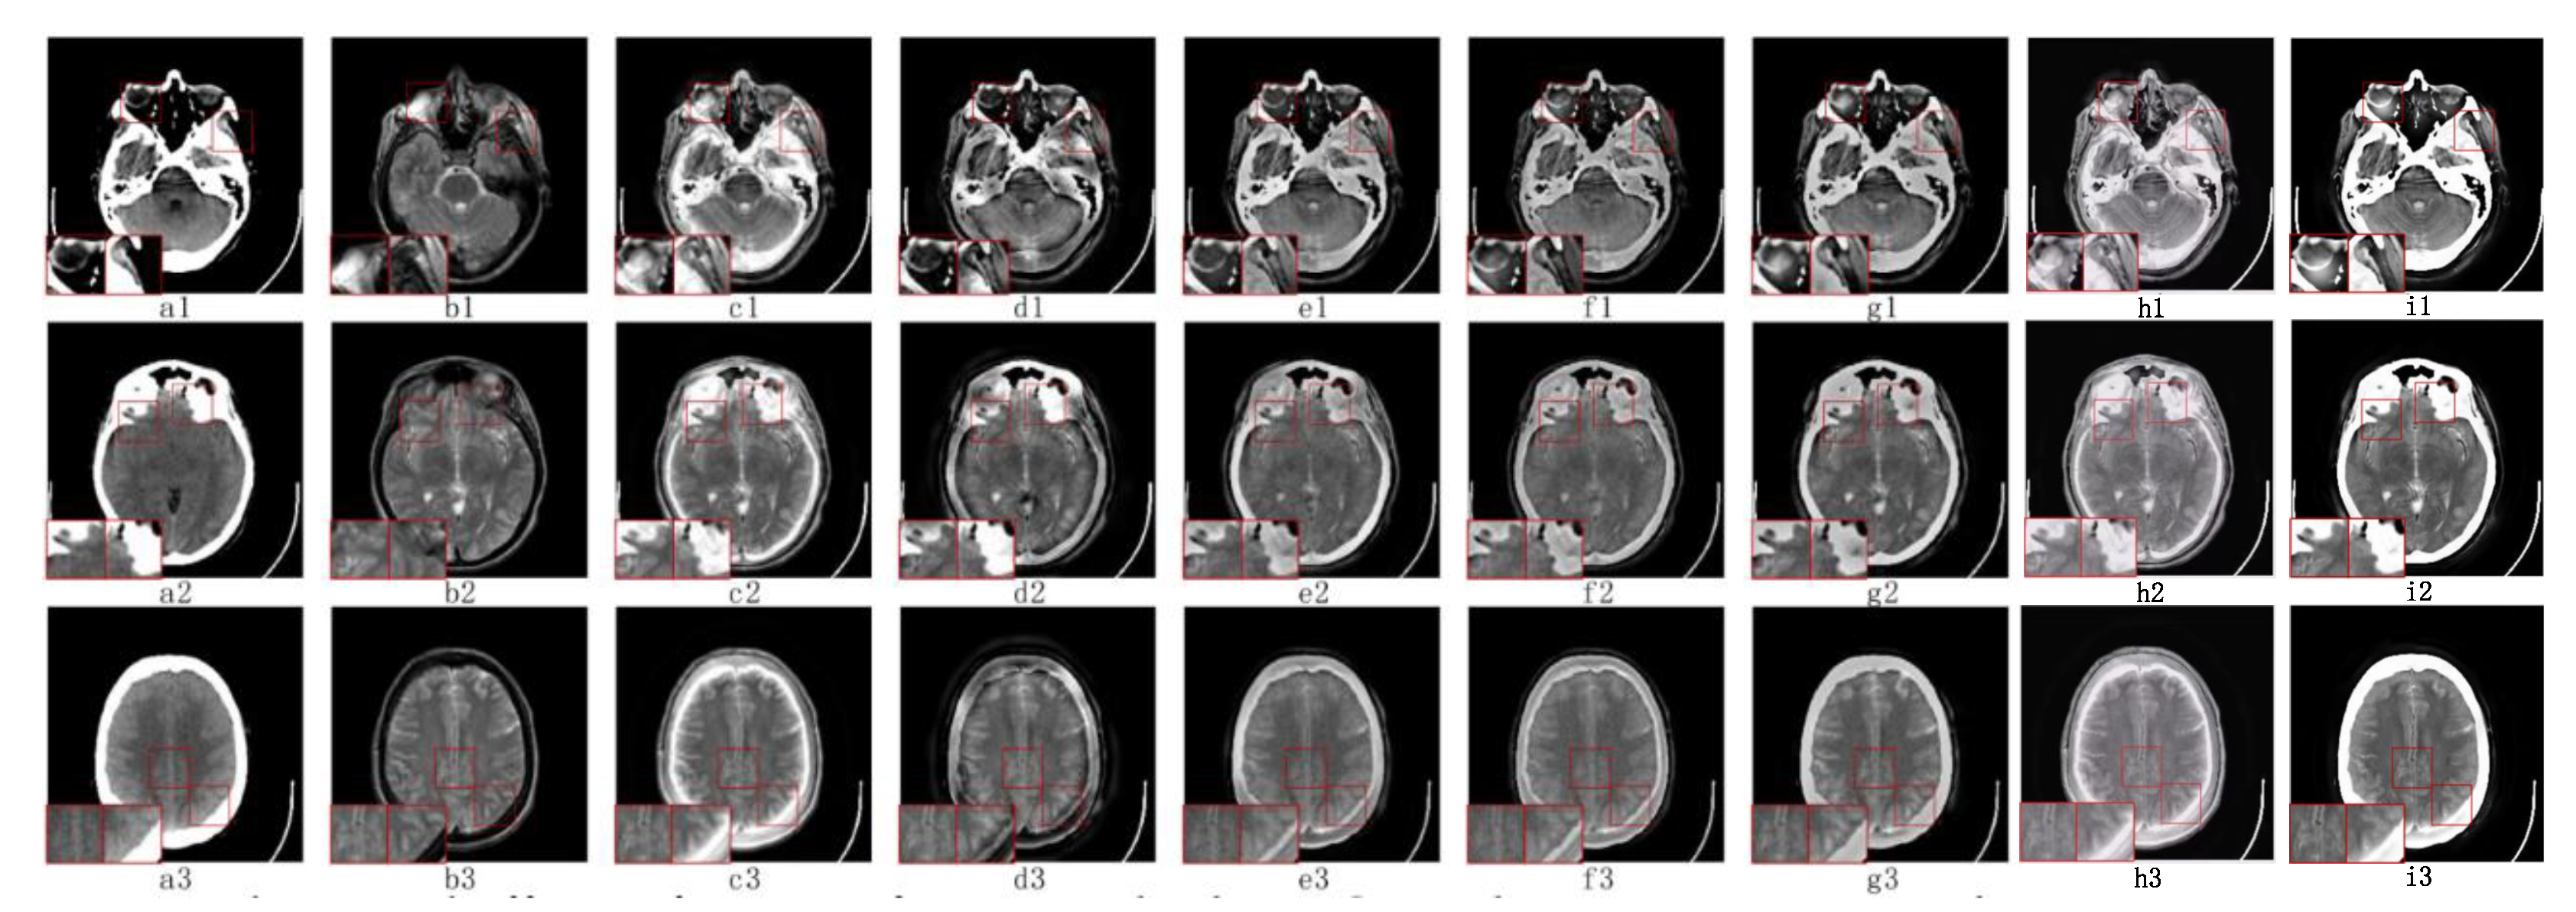

5.2.1. Fusion Analysis on T1-T2

5.2.3. Fusion Analysis on CT-MRI